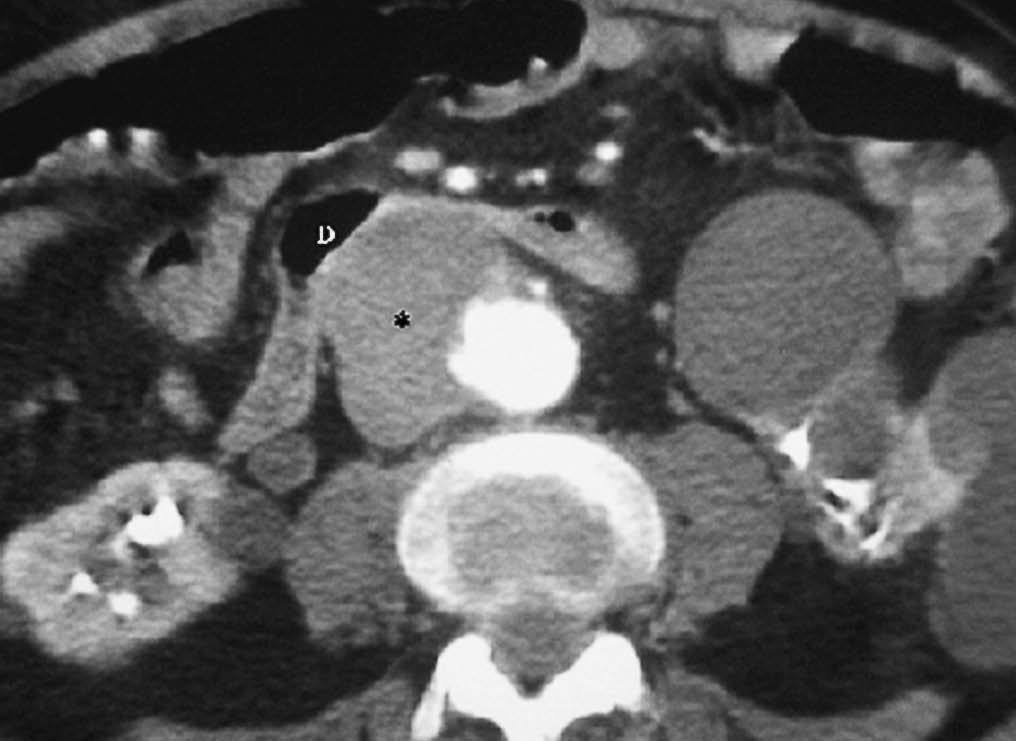

Una patología infrecuente es la fístula aortoduodenal, que se puede producir secundaria a un aneurisma de aorta en progresión o a procedimientos terapéuticos como la colocación de prótesis de aorta (fig. 15). En ocasiones puede observarse el paso de contraste de la aorta a la luz duodenal. Normalmente tiene una evolución fatal.

Fig. 15--Fístula aortoduodenal. Varón con hemorragia digestiva alta e imagen en tomografía computarizada con contraste intravenoso de aneurisma de aorta (*) que desplaza la luz duodenal (D) y con sangrado confirmado con endoscopia.